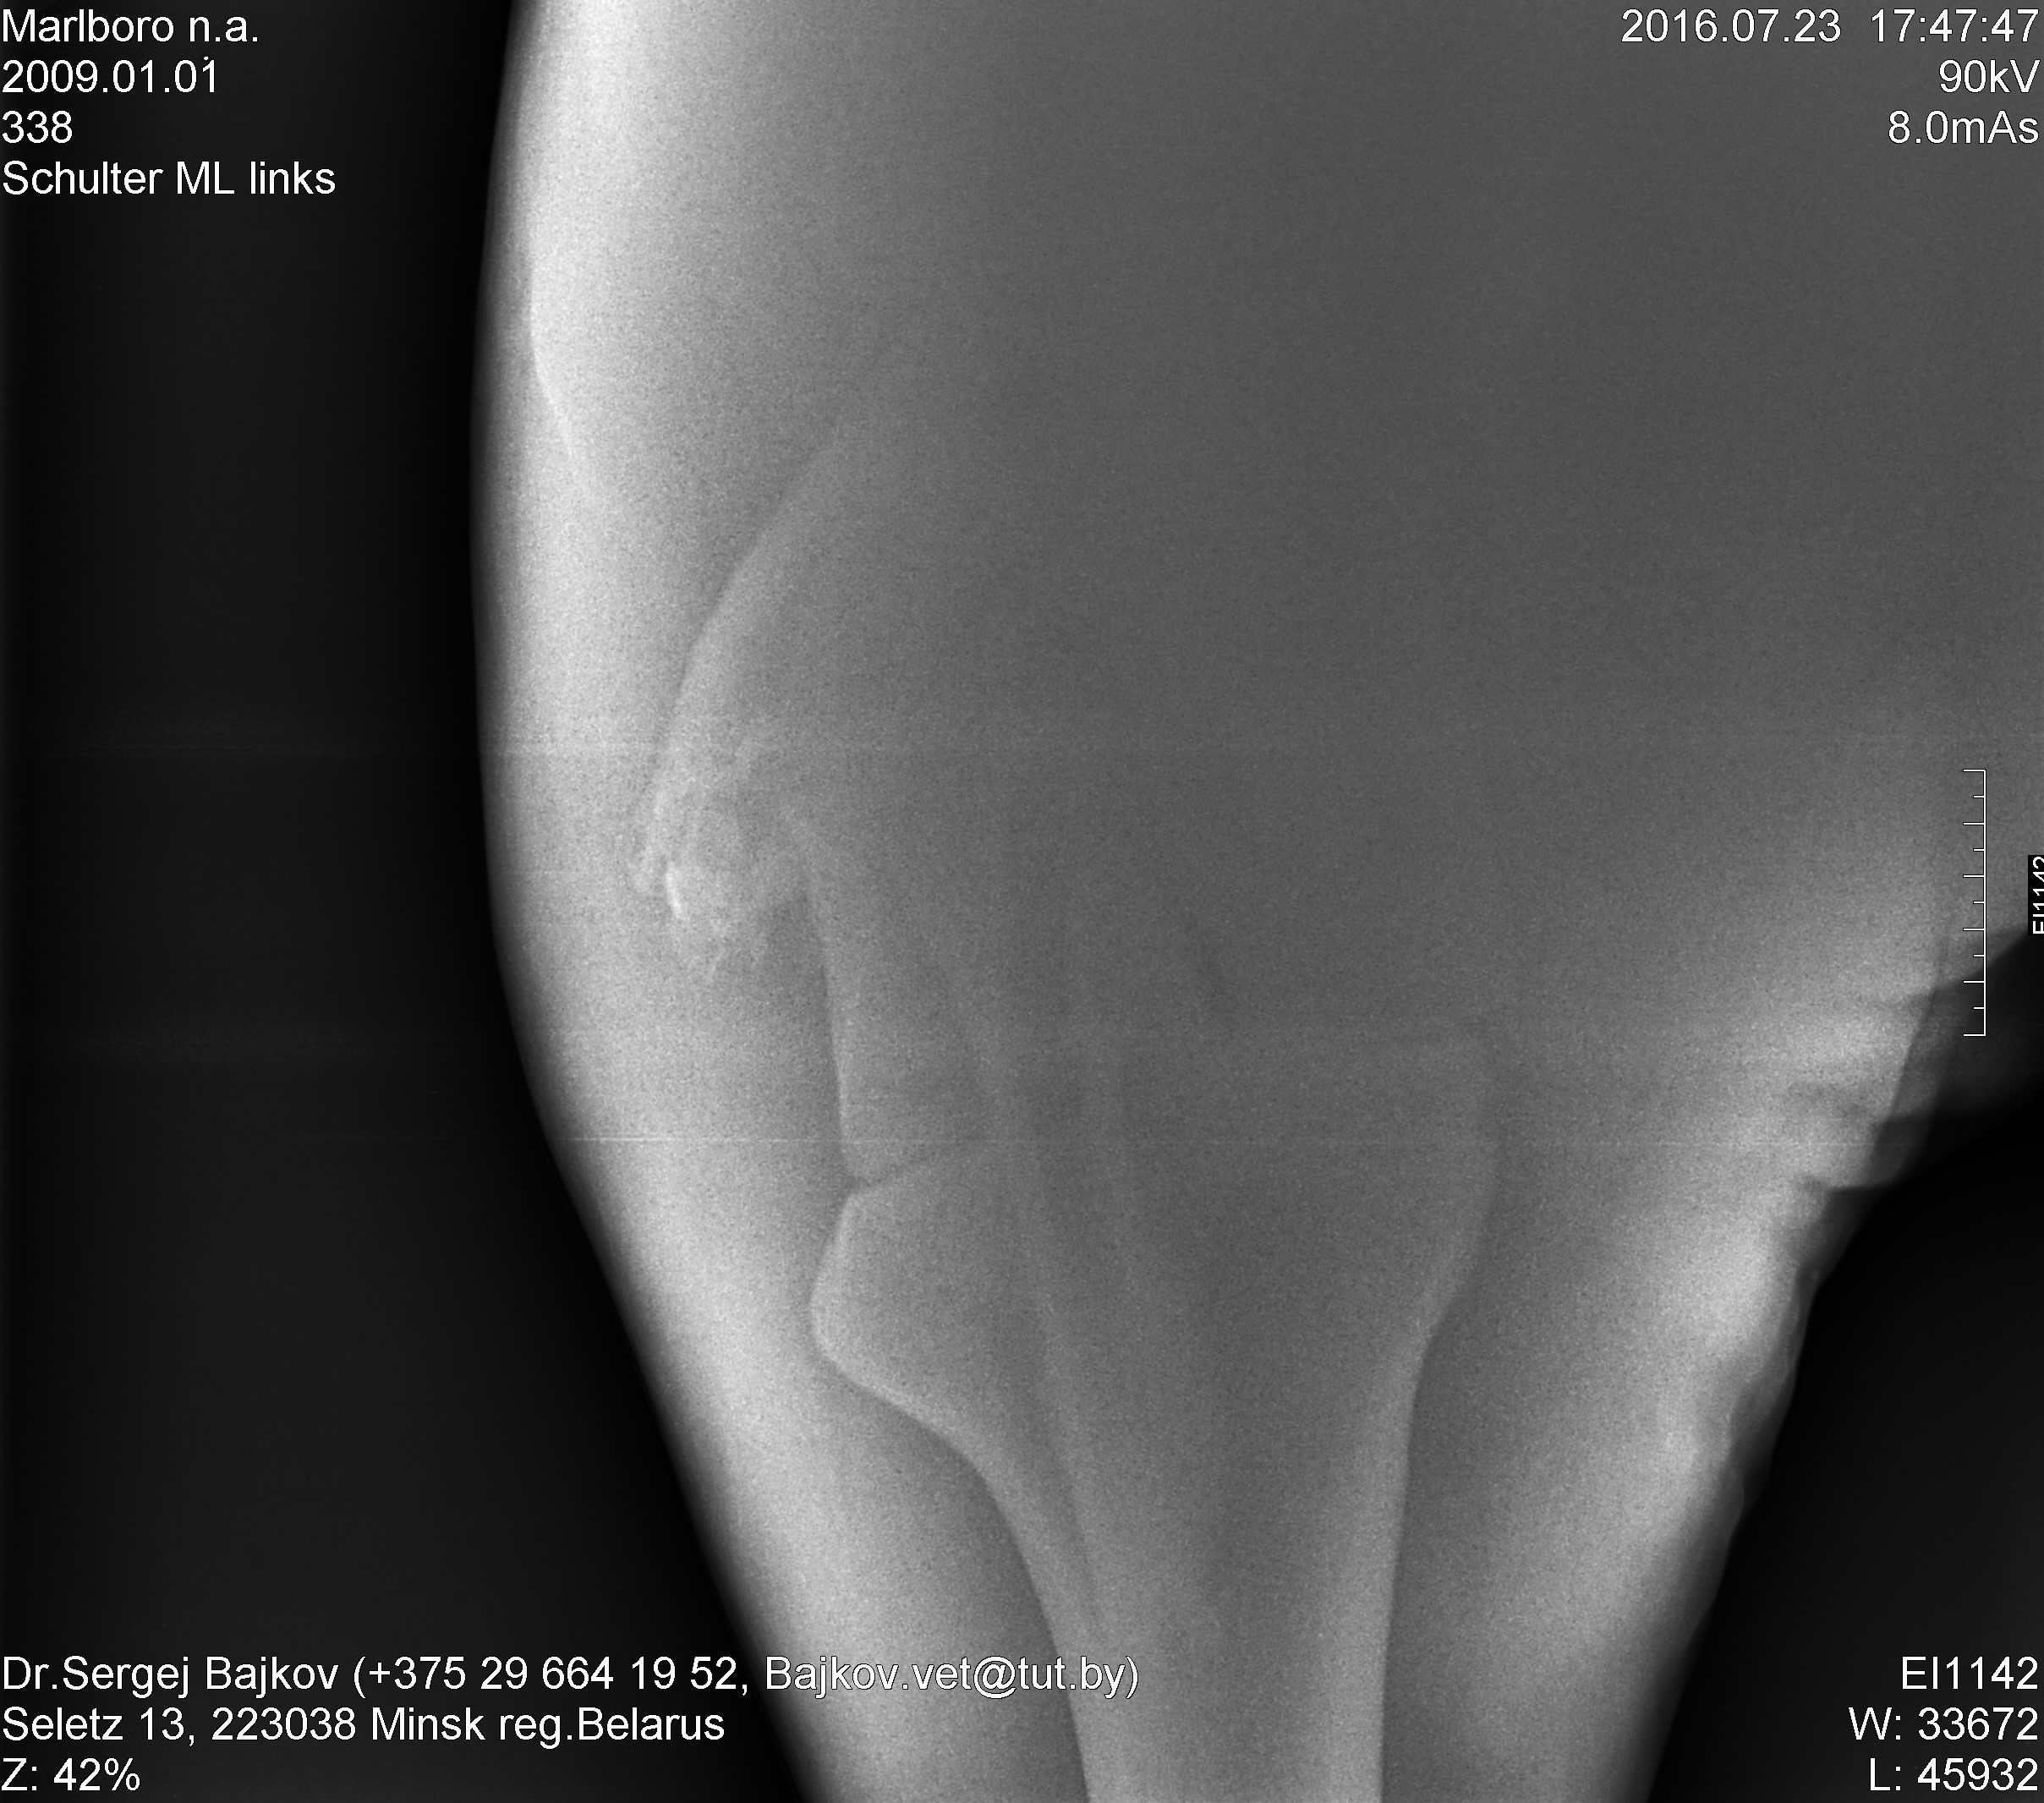

Наши снимки. К сожалению, снять получилось только нижний кусочек.

Докуда удалось достать -- все хорошо и по мнению оперировавшего хирурга, и по мнению Наташи-Кайхе.

Чуть позже выложу их комментарии.